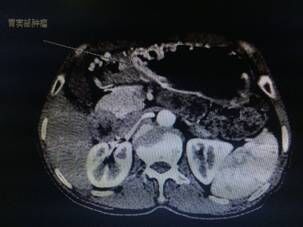

我院胃腸外科今年3月收治一名男性患者,以反復(fù)腹痛7月入院,CT提示胃竇部及乙狀結(jié)腸占位性病變(分別見圖1、2),行內(nèi)窺鏡活檢分別考慮胃腺癌以及乙狀結(jié)腸絨毛狀腺瘤,不排除惡變傾向。為改善患者生存率,減少創(chuàng)傷,手術(shù)團(tuán)隊決定充分發(fā)揮腹腔鏡技術(shù)優(yōu)勢,采用腹腔鏡下一期同時切除胃、結(jié)腸病變,由于患者乙狀結(jié)腸病變惡性診斷不明確,根據(jù)腫瘤根治的原則,先處理乙狀結(jié)腸。手術(shù)當(dāng)中依據(jù)冰凍切片,在腹腔鏡下首先完成乙狀結(jié)腸癌根治,后行腹腔鏡下遠(yuǎn)端胃癌根治術(shù)。一次微創(chuàng)手術(shù),切除兩個腫瘤,免除了患者傳統(tǒng)剖腹手術(shù)及二次手術(shù)的創(chuàng)傷,縮短了住院時間,術(shù)后恢復(fù)快,降低了患者住院費(fèi)用。

圖片1                               圖片2